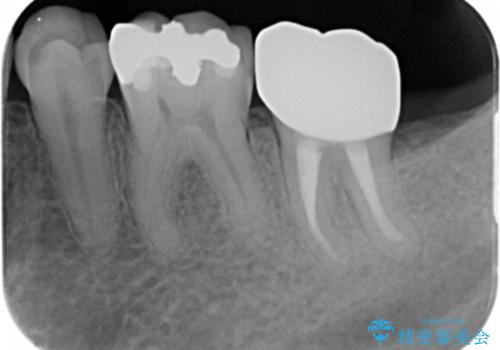

痛みなく噛めるようになり、歯の長期的な予後が期待できるような状態にすることができました。